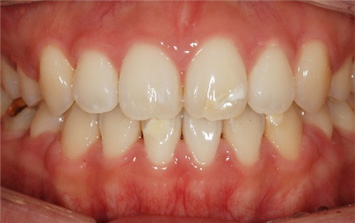

위 치열 후방이동으로 앞니의 치아 물림이 개선되었고, 앞니의 시림 증상도 사라졌습니다. 과개교합의 경우 환자 스스로 눈치 채지 못하는 경우가 많고,

사각 턱 안모가 동반되는 경우가 많기 때문에 꼭 정밀 검사를 받아보는 것이 좋습니다.